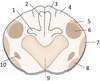

1

Q

1

2

3

A

1: Anterior Horn

2: Posterior Horn

3: Grey Commissure

2

Q

4

5

6

A

4: Anterior funiculus

5: Lateral funiculus

6: Posterior Funiculus